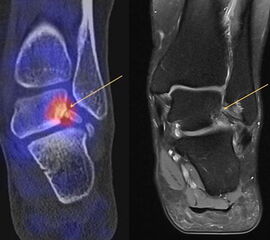

Abbildung 2.1.

Bildbeispiele symptomatische OCL

Zum Lesen der Bildbeschreibung und zur Vollansicht bitte das Bild anklicken. Bild: H. C. Rischke

Abbildung 2.2.

Bilder eines Patienten mit Z. n. mehrfachen Sprunggelenksdistorsionen in der Vergangenheit, besonders heftige Distorsion des linken Sprunggelenkes 5 Wochen vor der Untersuchung. Die SPECT/CT zeigt eine instabile osteochondrale Läsion mit deutlicher Aktivierung.

Abbildung 2.3.

Klärung bei Schmerzen im rechten OSG bei OCL an der medialen Talusschulter. Z. n. OSG-Distorsion vor 2 Jahren und Z. n. OSG-Fraktur / Syndesomosenruptur. Ausgedehnte OCL, hier jedoch kein erhöhter Knochenmetabolismus; lediglich Nachweis einer Stressreaktion im Bereich der Synchondrose eines Os trigonum als Schmerzursache.